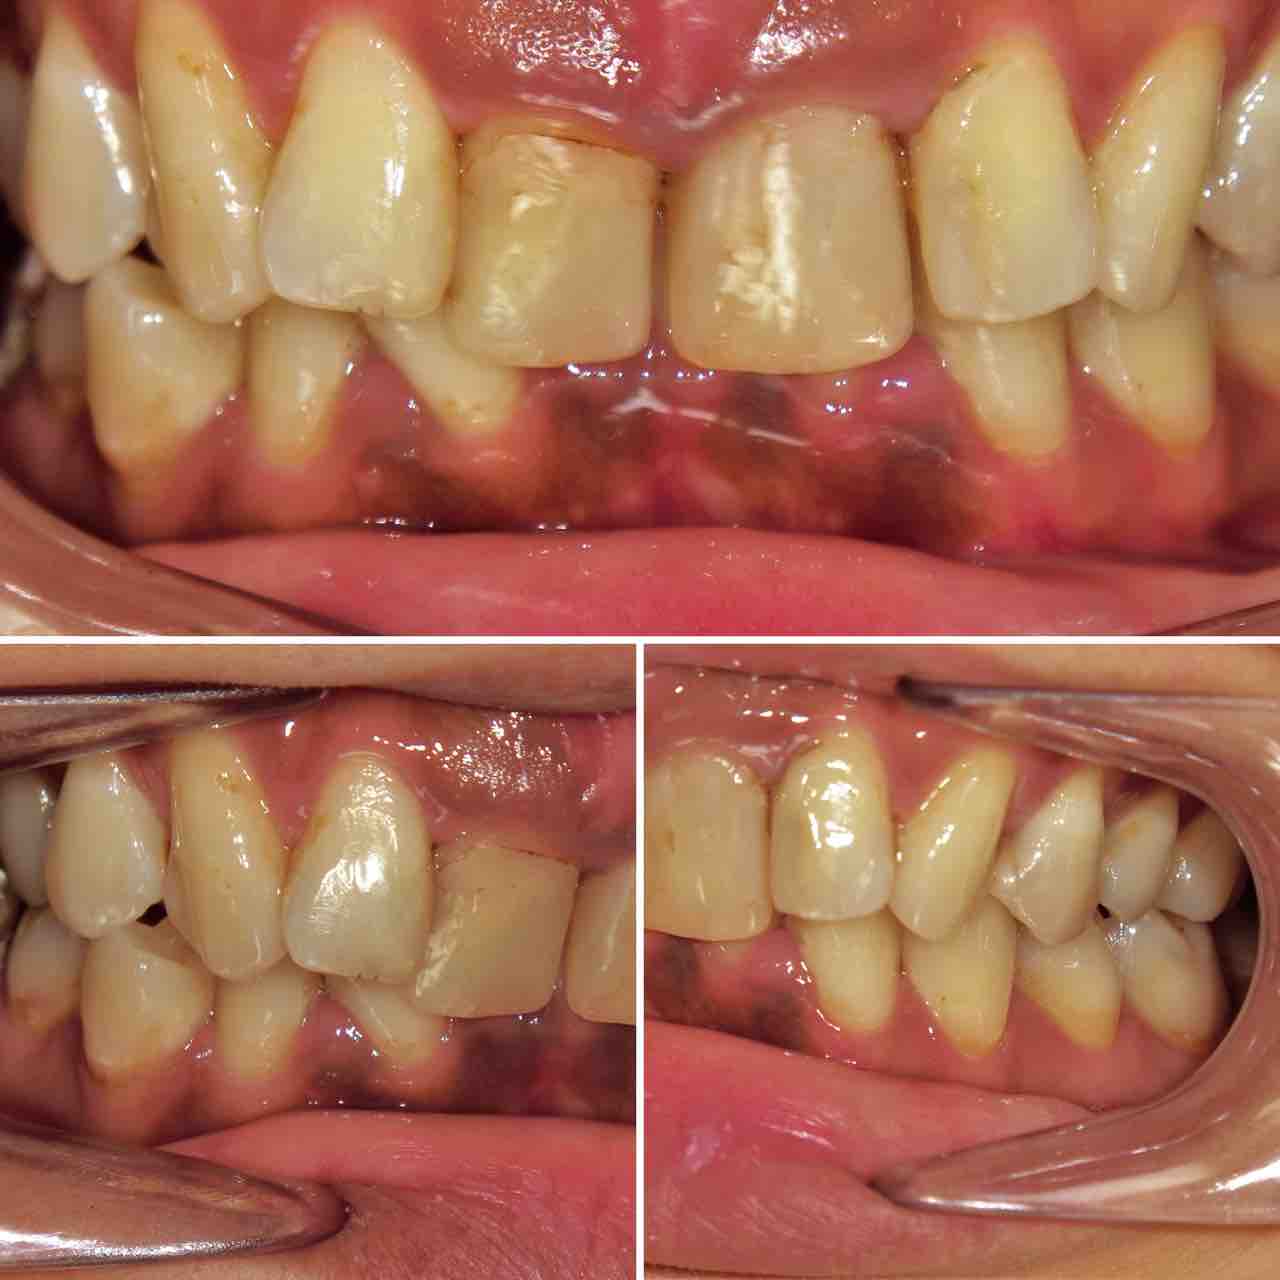

インビザラインで治療を終了した10代の患者さんのケースをご紹介する。

2024年4月5日に治療をスタートした。

内側に引っ込んだ歯を治したいという希望だった。

上の歯。前歯に内側に引っ込んだ歯がある。

下の歯にも同様に引っ込んだ歯がある。

横から見ると少し前歯が出っ歯気味になっている。

患者さんは平成23年生まれの13歳とあごの成長が残っている世代だった為、あごの成長をコントロールすることもできわずか10か月で終了することができた。